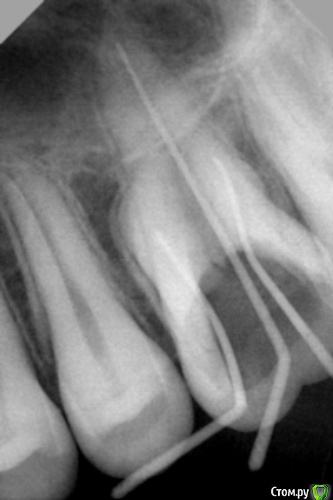

dr.Dre Опубликовано 20 августа, 2015 Поделиться Опубликовано 20 августа, 2015 (изменено) Добрый день пациент 14 лет,глубокий кариес,препарировал сразу провалился.Ситуация такая в дистальном канале очень сильная кальцификация максимум на эту длину прошел.Коллеги как поступить в даной ситуации?Спасибо Изменено 20 августа, 2015 пользователем dr.Dre Ссылка на комментарий

DOCTORARSEN Опубликовано 20 августа, 2015 Поделиться Опубликовано 20 августа, 2015 Добрый день пациент 14 лет,глубокий кариес,препарировал сразу провалился.Ситуация такая в дистальном канале очень сильная кальцификация максимум на эту длину прошел.Коллеги как поступить в даной ситуации?СпасибоКак правило, на такой глубине корневого канала облитераций не бывает. Думаю вы там сделали ступеньку. Вам нужно подгибать 8 или 10 К-File и попробовать пройти ступеньку. Ссылка на комментарий

Fred Опубликовано 20 августа, 2015 Поделиться Опубликовано 20 августа, 2015 В дистальном, или в МБ? По-моему, тут в МБ беда. 1 Ссылка на комментарий

St. Опубликовано 20 августа, 2015 Поделиться Опубликовано 20 августа, 2015 В 14 лет и на середине канала - скорее ступенька. Пробуйте обойти или показать колегам. Ссылка на комментарий

Fred Опубликовано 20 августа, 2015 Поделиться Опубликовано 20 августа, 2015 Понятно. Чтобы такого не случалось, нужно обрезать штифты делая снимок. Непройденный канал на такую длину как в ДБ в молодом возрасте при пульпите даст меньше вероятностей осложнений, чем попытки его во что бы то не стало найти. МБ2 поищите, тот у молодых широкий, он более вероятно даст беду, нежели пара мм в ДБ ... Ссылка на комментарий